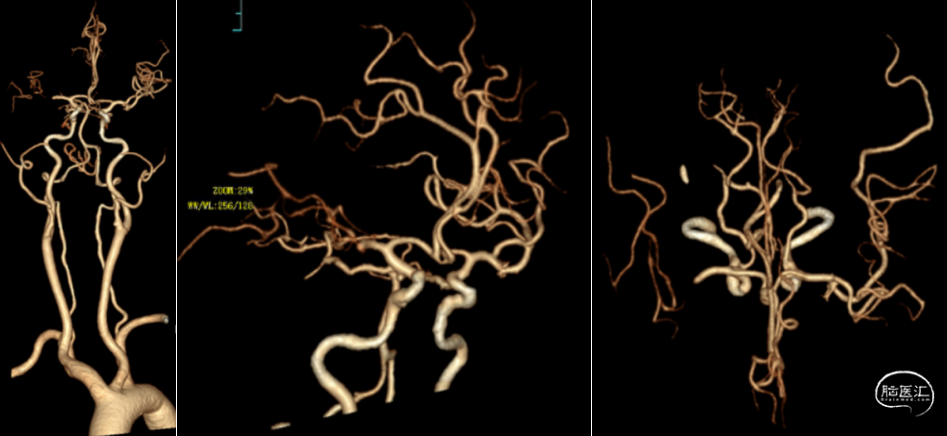

术前CTA+CTP示:1.右侧大脑中动脉M1段闭塞,前交通开放,右侧后交通开放;2.右侧大脑中动脉供血区大面积TTP、MTT延长,CBF降低,CBV减低。

术前造影

术后造影